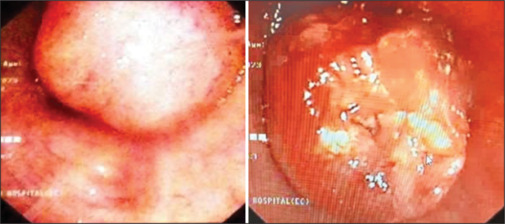

肺错构瘤是最常见的肺良性肿瘤,通常是偶然发现的。支气管内错构瘤虽然罕见,但可引起明显的症状,如呼吸困难、咯血和支气管阻塞引起的反复呼吸道感染。本报告描述两名年龄分别为29岁和34岁的年轻印度男性成功的支气管镜治疗有症状的支气管内错构瘤。这两个病例都是根据放射学和组织病理学结果诊断的。第一名患者使用柔性支气管镜进行了8次电灼,而第二名患者通过柔性支气管镜引导的冷冻探针进行了6次冷冻治疗。所有手术均在清醒镇静下进行,通过柔性支气管镜鼻腔插入,不需要刚性支气管镜或全身麻醉。两例患者均表现出明显的症状改善和支气管内病变几乎完全消退。分别在18个月和12个月随访支气管镜检查,未发现复发,也未观察到手术相关并发症。这些病例强调了柔性支气管镜技术如电灼和冷冻消融治疗支气管内错构瘤的安全性、有效性和微创性,特别是在手术选择可能有限的情况下。

Pulmonary hamartomas are the most common benign tumours of the lung and are often detected incidentally. Endobronchial hamartomas, though rare, can cause significant symptoms such as dyspnoea, haemoptysis, and recurrent respiratory infections due to bronchial obstruction. This report describes the successful bronchoscopic management of symptomatic endobronchial hamartomas in two young Indian males aged 29 and 34 years. Both cases were diagnosed based on radiological and histopathological findings. The first patient underwent eight sessions of electrocautery fulguration using a flexible bronchoscope, while the second was treated with six sessions of cryotherapy delivered through a flexible bronchoscope guided cryoprobe. All procedures were carried out under conscious sedation via nasal insertion of the flexible bronchoscope, with no requirement for rigid bronchoscopy or general anaesthesia. Both patients showed marked symptomatic improvement and near-complete resolution of endobronchial lesions. Follow-up bronchoscopies at 18 and 12 months, respectively, revealed no recurrence, and no procedure-related complications were observed. These cases highlight the safety, efficacy, and minimally invasive nature of flexible bronchoscopic techniques such as electrocautery and cryoablation in managing endobronchial hamartomas, particularly in settings where surgical options may be limited.